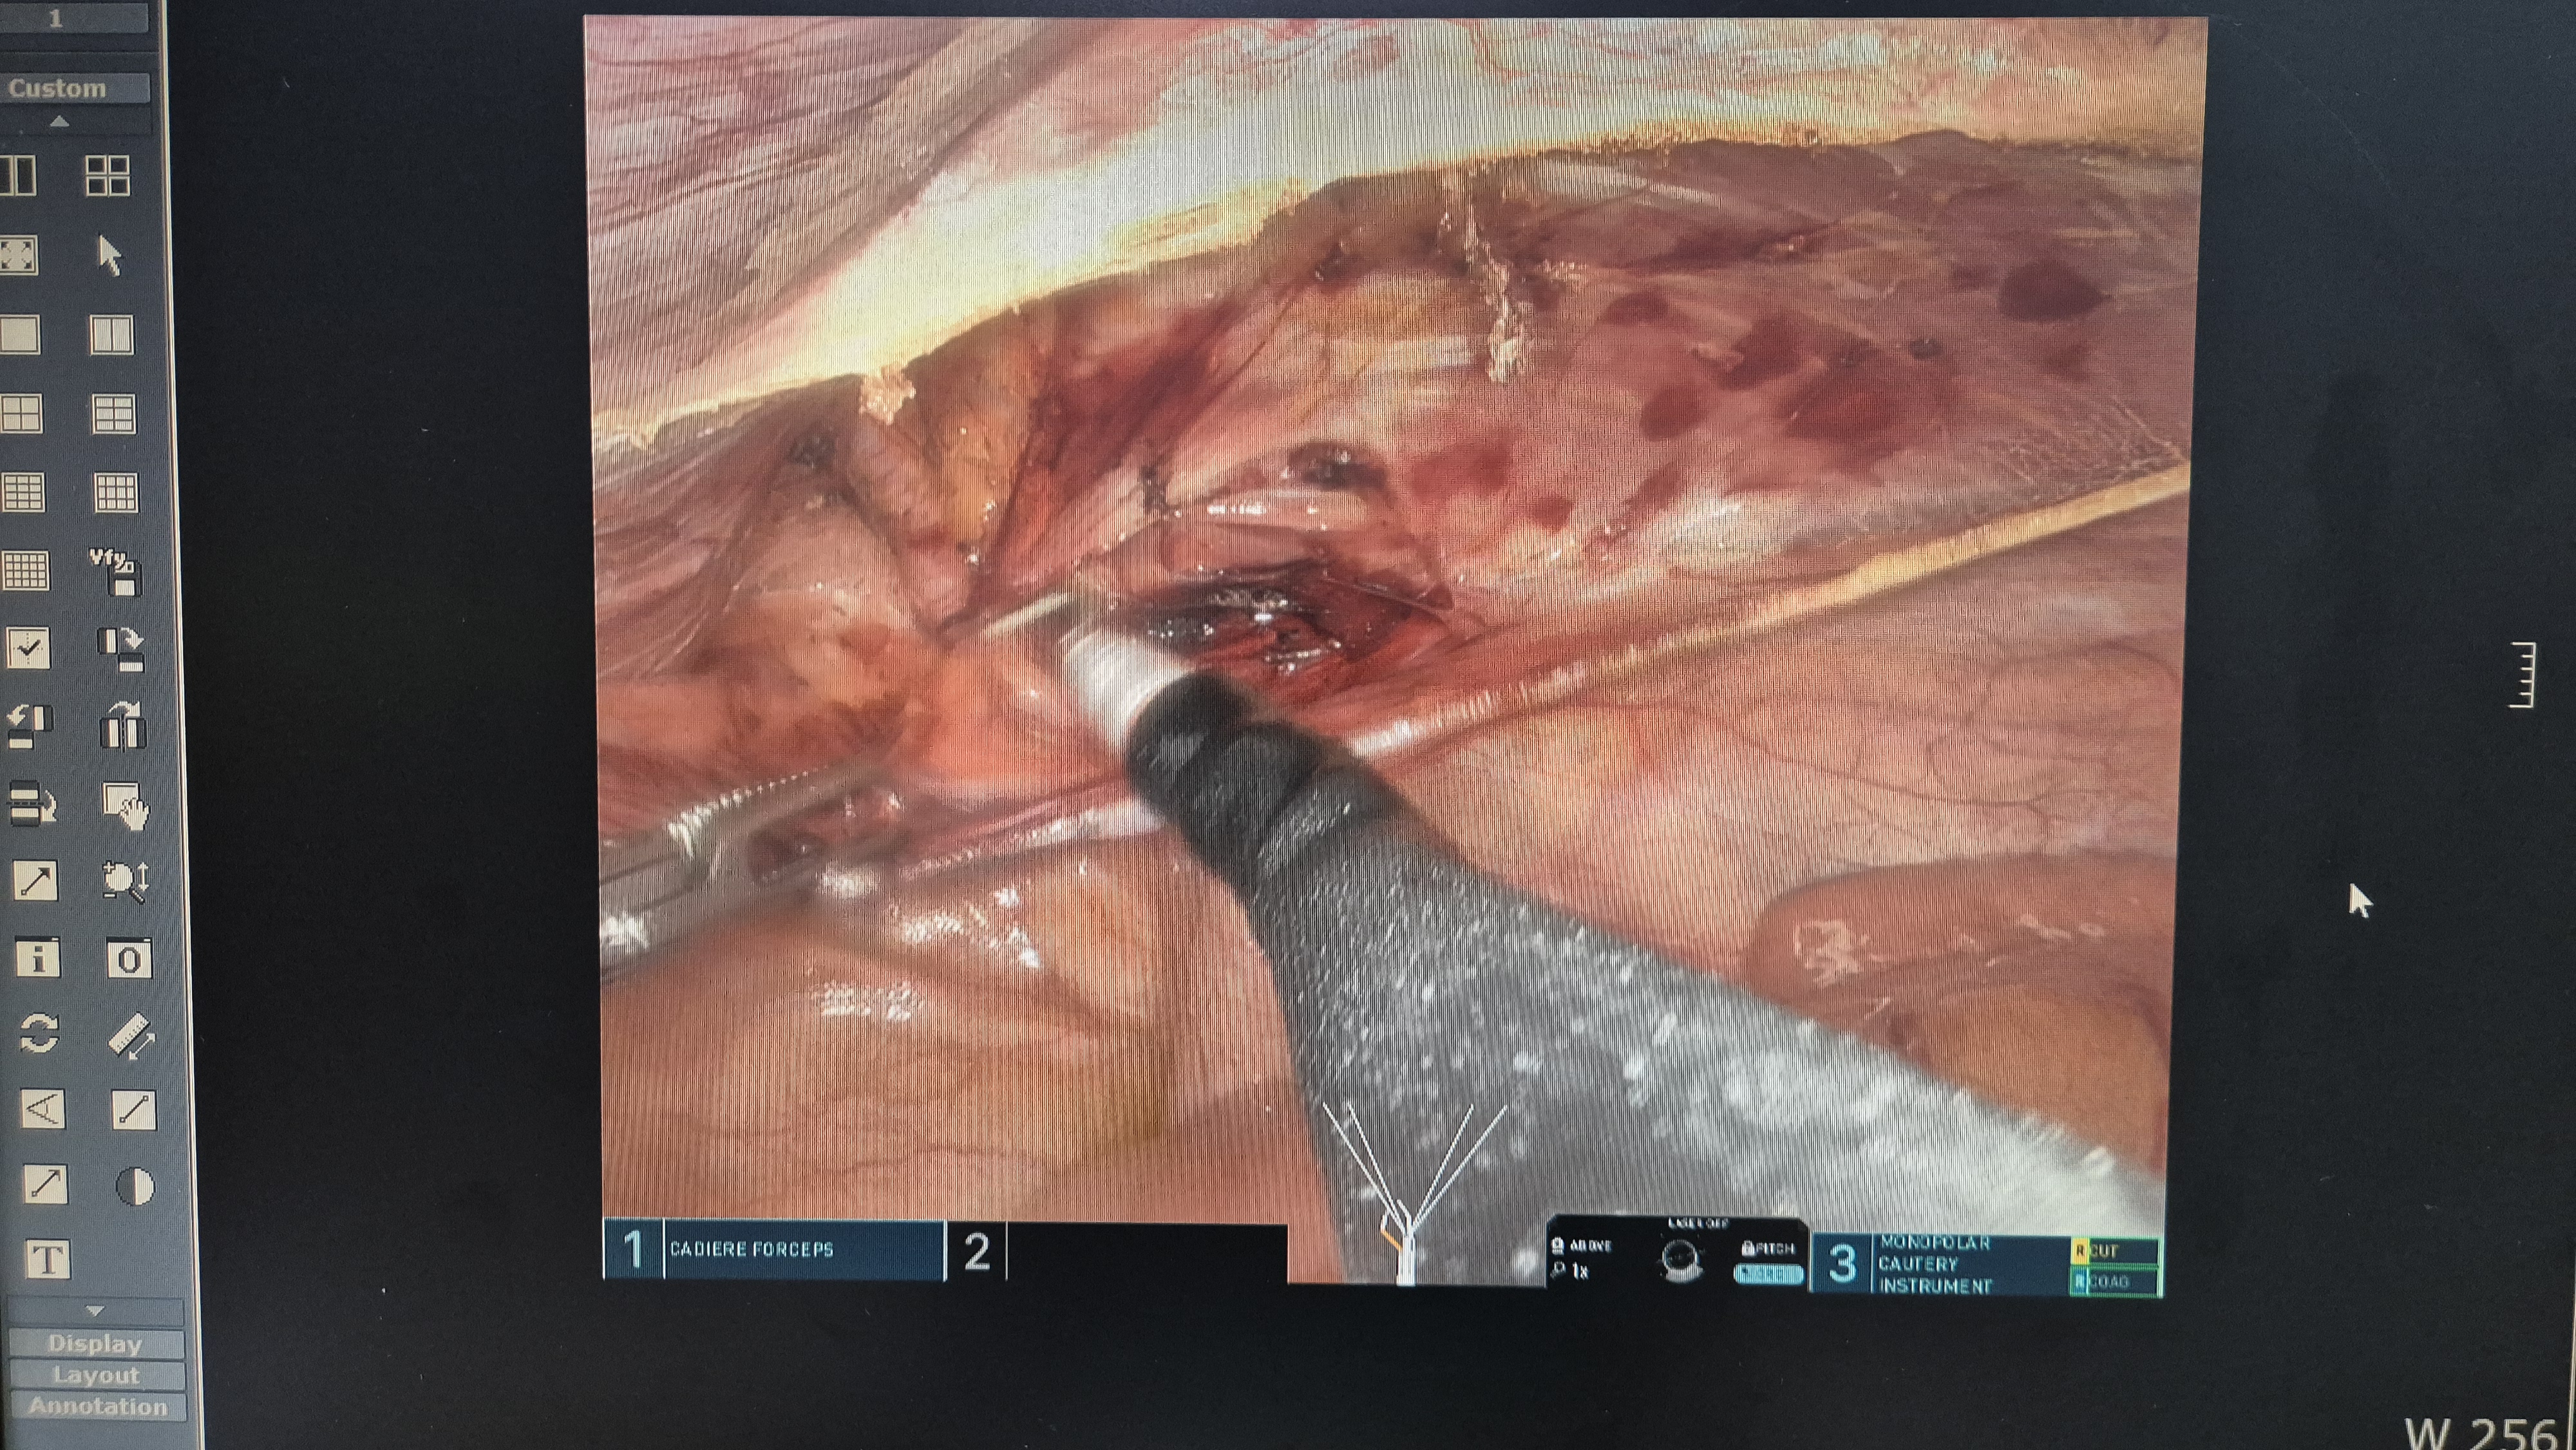

복막을 열고.